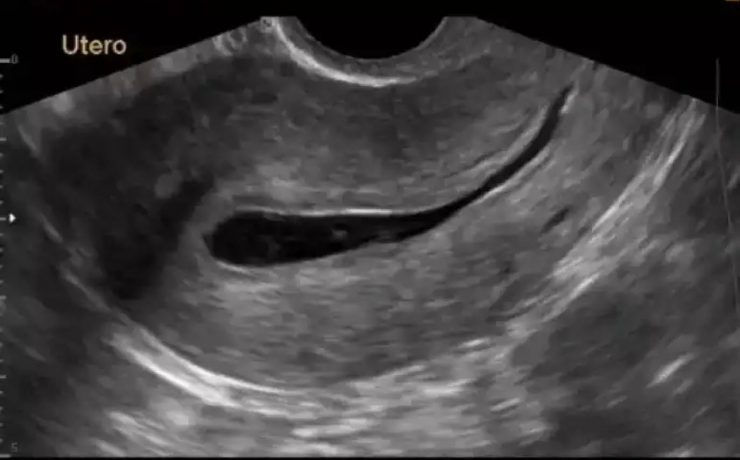

Onfalocele fetal

El onfalocele o exónfalo es un defecto en el desarrollo de la pared abdominal, en el que las vísceras herniadas están cubiertas por peritoneo, amnios y gelatina de Wharton. Los órganos comprometidos en la evisceración pueden ser asas de intestino delgado o grueso, hígado y estómago, estando siempre incluido el